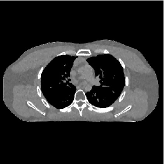

This section compares the reconstruction quality and runtime among the proposed MBIR method, PWLS-ST-, and other three MBIR methods, PWLS-EP, PWLS-DL, and PWLS-ST-. Table I shows that, for both 2D and 3D sparse-view CT reconstructions of the XCAT phantom, the proposed PWLS-ST- model outperforms PWLS-EP and PWLS-ST- in terms of RMSE. In addition, PWLS-ST- using a square transform (of size ) achieves lower RMSE than PWLS-DL using an overcomplete dictionary (of size ) for 2D sparse-view reconstructions. Fig. 3(a) and Fig. 4 show the reconstructed images for 2D and 3D phantom experiments, with different reconstruction models and different number of views. (See the corresponding error maps in the supplement.) The proposed PWLS-ST- consistently gives more accurate image reconstructions compared to other MBIR methods. Specifically, PWLS-ST- has smaller errors in the heart region (see zoom-ins in Fig. 3(a)) of 2D reconstructions than PWLS-DL and PWLS-ST-. In addition, compared to PWLS-ST-, PWLS-DL and PWLS-ST- have some ringing artifacts around the edges with high transition, e.g., edges between air and soft tissues. (See a comparison of profiles of PWLS-ST- and PWLS-ST- in the supplement.) In particular, PWLS-ST- and PWLS-DL give more visible ringing artifacts for 2D reconstruction from fewer views, and PWLS-ST- has these ringing artifacts for 3D reconstructions regardless of the number of views (see zoom-ins in Fig. 4). Table II reports runtimes of different MBIR methods in reconstructing the -views XCAT phantom scan. (FBPConvNet is a non-MBIR method and its runtime for processing a image is approximately one second with a TITAN Xp GPU.) While providing better reconstruction quality, the proposed Algorithm 1 of PWLS-ST- has shorter runtime compared to the algorithms of PWLS-DL and PWLS-ST- in Section III-A. Similar to the PWLS-EP algorithm, the reconstruction time of the PWLS-DL, PWLS-ST-, and PWLS-ST- algorithms can be further reduced by using ordered subsets [51].

![]() |

| (a) 2D fan-beam CT experiments |

| (b) 3D axial cone-beam CT experiments |